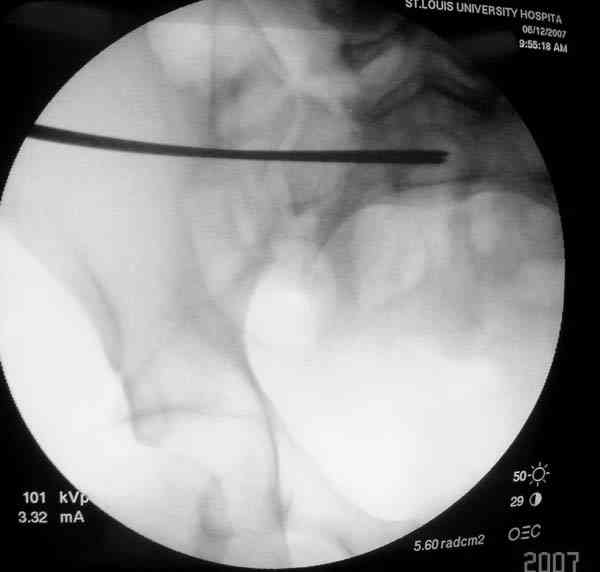

Применение длинных (7 мм каннюлированных, с резбой на всем протяжении от компании Mercury) шурупов, проведенных между двумя илиосакральными сочленениями нейтрализирует деформацию до наступления сращения.

Сверло-направитель в 3.2 мм проводится вручную без применения дрели, и длина в 46 см обычно достаточна до захвата следующего илио-сактрального сочленения.

Sacroiliac screw placement

Inlet view